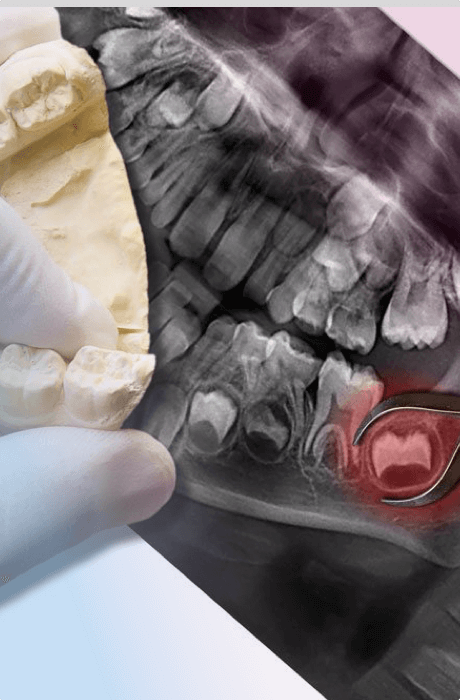

Удаление зубов мудрости

Если удаление обычных зубов – это результат запоздалого лечения или несчастного случая, то удаление «восьмерок» (зубов мудрости) – закономерное явление. Все потому, что эти зубы являются рудиментарными органами, то есть они утратили свое значение. В прежние времена «восьмерки» были необходимы человеку для пережевывания грубой сырой пищи, но сейчас ей на замену пришла мягкая и обработанная. Однако зубы мудрости по-прежнему продолжают расти.

На «восьмерках» быстро развиваются кариес и его осложнения. Это связано с положением зубов – они труднодоступны, поэтому их гигиена проходит менее тщательно.